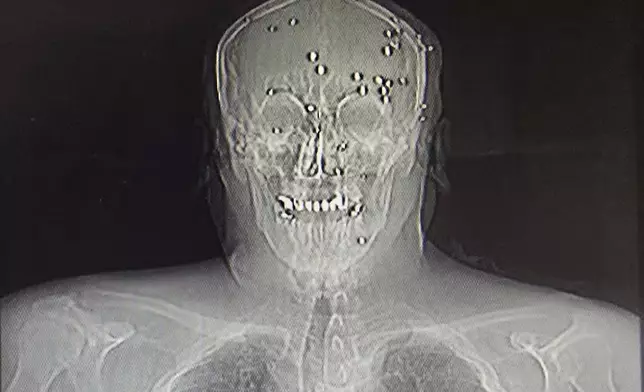

A family of four — a mother, father and their 8- and 10-year-old children — were all riddled with pellets, the surgeon said. The older boy had dozens of pellets in his face, but amazingly none hit his eyes.

On the morning of Jan. 9, the phone lines started working again, and the surgeon reached out to doctors he trusted to refer patients to them. First he had to make sure to remove all bullets and pellets from their bodies so they wouldn’t be detained at the hospital. He wrote referral letters saying the patients had been in car accidents.

This is a photo of an X-ray image taken Jan. 9, 2026, obtained outside Iran, showing an Iranian protester who was hit in the face by pellets in Rasht, northern Iran. (UGC via AP)